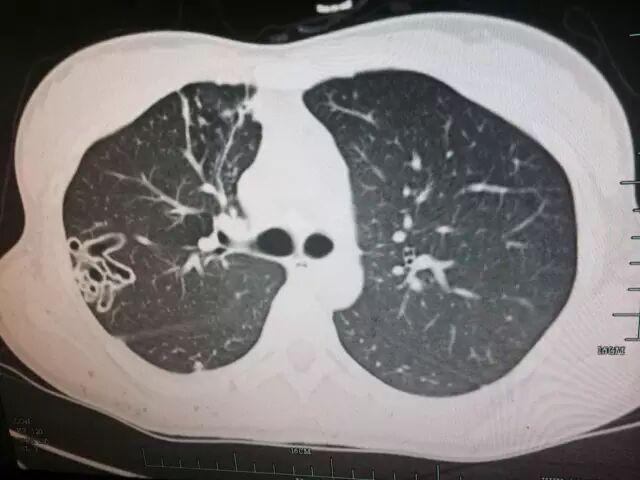

左下角就是被虫子钻空的“隧道”

(肺部CT图)

画圈部分就是被虫子钻空的“隧道”

接诊这起疑难杂症的正是徐旭东主任,他发现小夏的右肺有多个病灶,点开小夏的肺部CT资料,可以清楚地看到小夏的右肺上有很多空洞,像是打隧道凿出来的出口。医生又进行了结核等相关检查后,排除了结核病,但又给不出明确的诊断。

“人体寄生的肺吸虫,在国内有卫氏肺吸虫和斯氏肺吸虫两种。浙江省是肺吸虫特别是卫氏肺吸虫病的流行区,该病可通过生吃或半生吃淡水螃蟹、河里的虾、小龙虾等获得。发病后,患者可能出现咳嗽、呼吸困难、血痰、胸痛等症状,与结核病典型症状极为相似。”徐旭东主任解释道,肺吸虫被误诊为结核病的概率高达50%。“在小夏CT上看到的空洞,正是肺吸虫游走肺内留下的痕迹。”